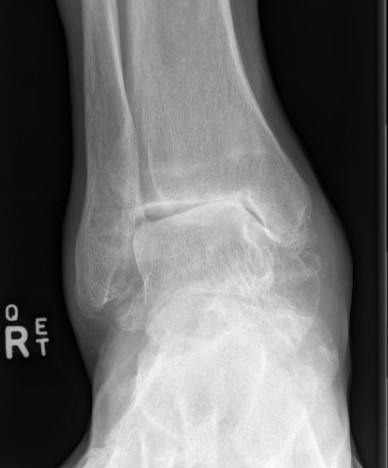

Xray

Ranges from anterior spurring to severe OA

80% of post-traumatic OA is varus

Takakura classification

| 1 | Early sclerosis and formation of osteophytes |

| 2 | Narrowing of the medial joint space |

| 3A | Obliteration of the medial joint space with subcondral bone contact |

| 3B | Obliteration of joint space over roof of talar dome, with subchondral bone contact |

| 4 | Obliteration of joint space with complete tibiotalar contact |

Type 1: Anterior spurs

Type 3A: Obliteration of medial joint space Type 3B: Obliteration medial joint space plus tibio-talar contact with varus

Type 4 complete obliteration